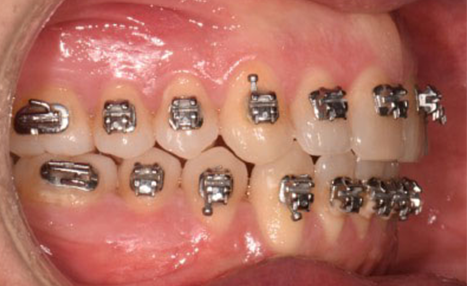

A 38-year-old male patient sought orthodontic treatment with both functional and esthetic concerns. His main complaints included the appearance of an inverted smile arc, reduced incisor display, and a general lack of harmony in his smile.

The extraoral examination revealed a long facial type with an increased lower facial third, nasolabial folds accentuated by insufficient midface support, and broad buccal corridors due to maxillary compression. Intraoral analysis showed a posterior crossbite, negative torque on posterior teeth, and an altered occlusal balance. Radiographic and cephalometric evaluation confirmed the clinical findings, with an increased mandibularplane angle and mandibular posterior rotation. This rotation contributed to a convexity of +4 mm, although the underlying problem was a retruded maxilla with insufficient midface support. Vertical facial height was also increased. Importantly, the temporomandibular joint evaluation showed a posterior condylar position with intact cortical bone, no pain, and no joint sounds.

(Images: Intraoral Initial)